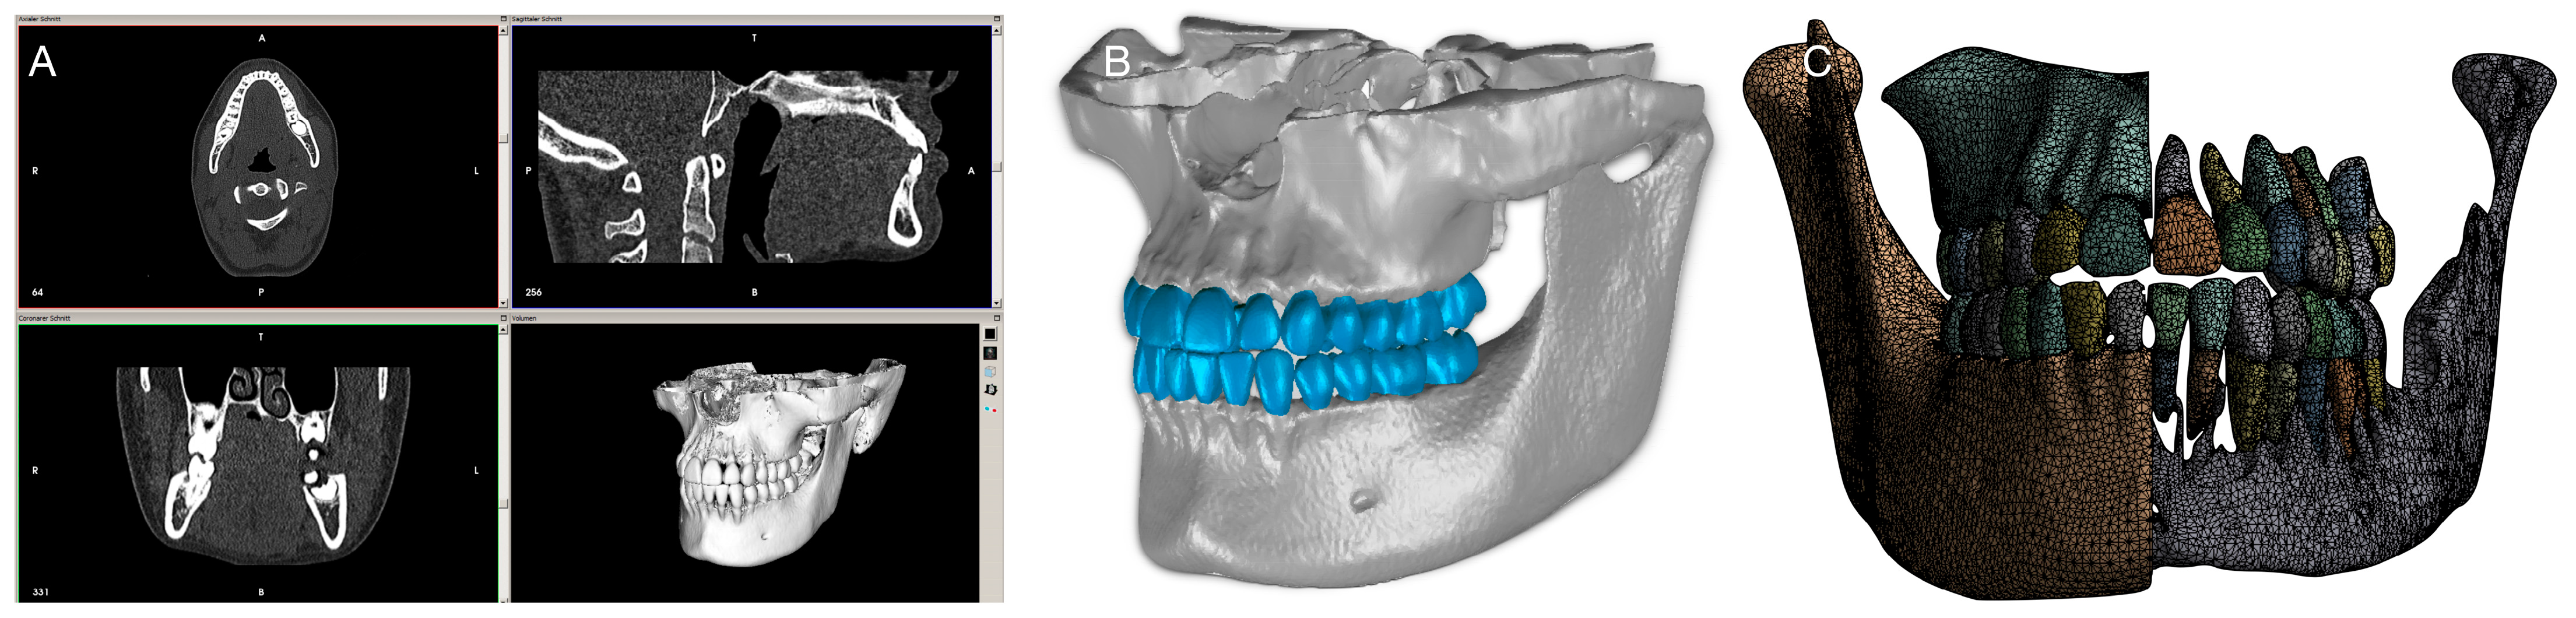

2. Materials and Methods